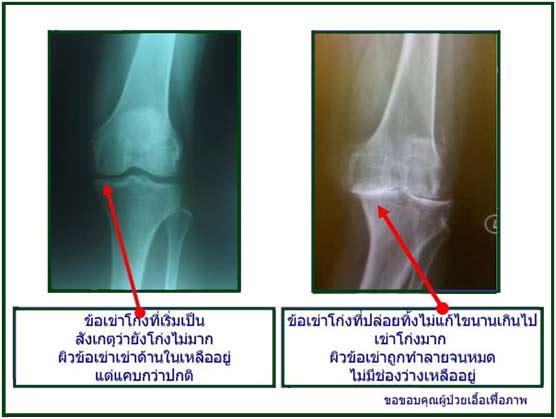

1. กระดูกอ่อนที่ผิวข้อด้านในอาจจะสึกเร็วกว่าปกติ (Medial Compartment knee Joint Destruction)

น้ำหนักตัวที่กดลงมาข้อเข่าที่โก่ง จะไม่ถูกกระจายไปที่ผิวข้ออย่างที่ควรจะเป็นครับ แต่จะกระจุกตัวอยู่ที่ฝั่งด้านในของเข่าทั้งสองข้าง เมื่อแรงกระเทือนที่ข้อเข่าเกิดขึ้นซ้ำ ๆ กันหลาย ๆ หน (คนเราเดินเฉลี่ยวันละ 5,000-8,000 ก้าว)

บวกกับปัจจัยเสี่ยงที่เจ้าของข้อเข่ามีอายุเพิ่มขึ้นทุกปี แต่มีกล้ามเนื้อต้นขาที่อ่อนแอลงไป กระดูกอ่อน (cartilage cell) ที่ผิวสัมผัสของข้อเข่าก็จะรับแรงกระเทือนนี้ต่อไปไม่ไหว จนกระดูกอ่อน ฝั่งนี้สึกกร่อนมากขึ้นเรื่อยๆ ข้อเข่าก็จะเอียง แถมมีผลสมทบทำให้มุมเข่าโก่ง แล้วเพิ่มมากขึ้นเข้าไปอีก แรงกดที่กระดูกอ่อนฝั่งด้านในจึงเพิ่มขึ้นทุกปีเป็นเงาตามตัว เป็นวงจรแบบนี้ไม่รู้จบ จนผู้ป่วยเริ่มมีอาการปวด บวมเข่าให้เห็น สุดท้ายจึงเริ่มมีอาการของ โรคข้อเข่าเสื่อมก่อนวัย (Knee Osteoarthritis in Young Adult)